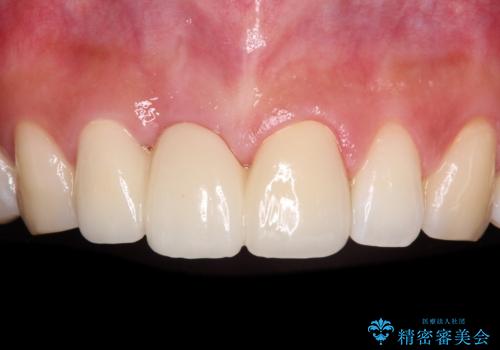

【モニター】前歯のデコボコと奥歯の虫歯 インビザライン治療と奥歯のセラミック治療

下顎前歯の叢生が速やかに改善されたため、1年3か月で治療を終えることができました。

下顎前歯は後戻りを起こしやすいため、舌側を細いワイヤーで固定することで後戻り対策を行っています。